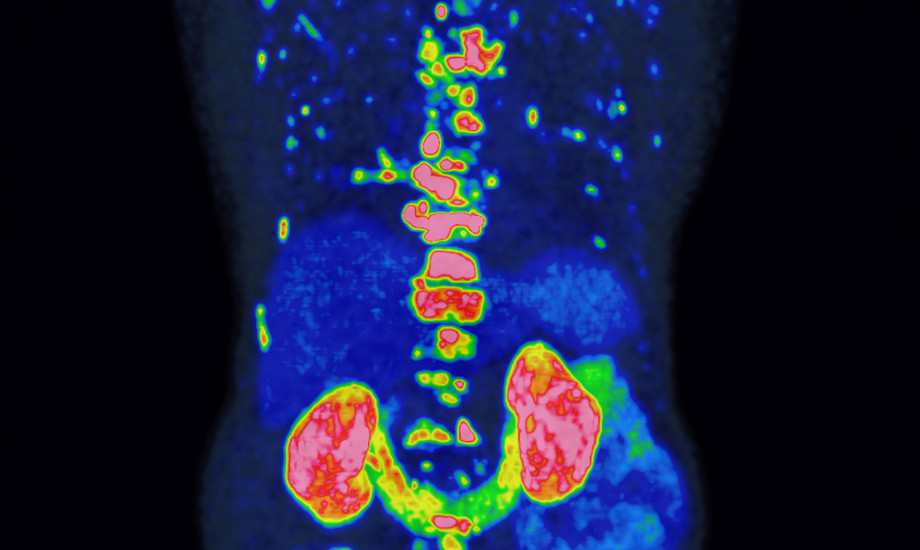

Die Deutsche Hochschulmedizin zeichnet 2025 die internationale Forschungsinitiative PROMISE aus. Das Team hat eine Methode entwickelt, mit der sich der Verlauf von Prostatakrebs mittels hochauflösender Bildgebung genauer vorhersagen und die Therapie individueller steuern lässt.

© Prof. Dr. Wolfgang Fendler / UDE, Prof. Dr. Wolfgang Fendler